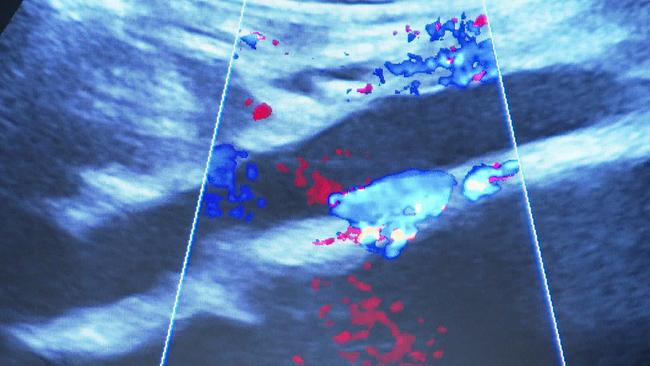

Ein Bauchaortenaneurysma ist eine gefährliche, aber oft unbemerkte Erweiterung der Hauptschlagader im Bauch, die unbehandelt lebensbedrohlich werden kann. Da die Erkrankung meist keine Symptome verursacht, ist eine frühzeitige Erkennung entscheidend.

Ultraschalluntersuchungen ermöglichen eine schmerzfreie, risikoarme Diagnostik, mit der ein Aneurysma bereits in frühen Stadien entdeckt werden kann. Bei Bedarf stehen effektive Behandlungsmöglichkeiten zur Verfügung, darunter die offene Operation oder das schonendere endovaskuläre Verfahren mittels Stent.

Expert*innen betonen, dass insbesondere Männer ab 55 Jahren und Personen mit Bluthochdruck oder familiärer Vorbelastung von einem Screening profitieren.